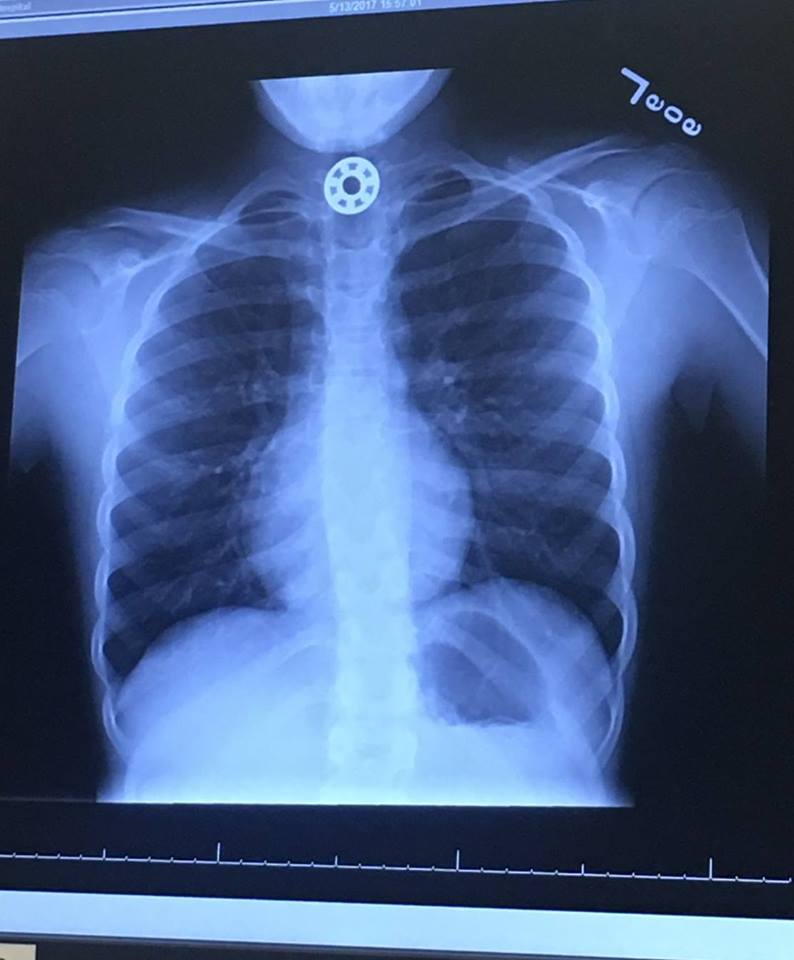

A Houston, Texas-area mother posted a lengthy story on Facebook about how her 10-year-old daughter swallowed a piece of her fidget spinner and had to be taken to an urgent care facility.

Luckily, all ended well for the child, who is now doing fine. But, this should serve as a potential warning to distributors (and parents) looking to incorporate fidget spinners into promotional campaigns aimed at children. Similar to the magnetic balls that Zen Magnets destroyed, these include small pieces that children could accidentally ingest.